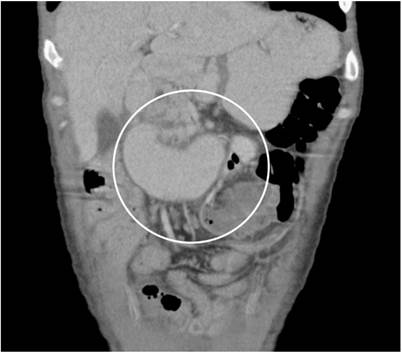

A 25-year-old man diagnosed with a non-seminomatous germ cell tumor was admitted to the emergency department for diffuse abdominal pain associated with bloating and multiple emetic episodes. Due to the clinical suspicion of intestinal obstruction, a contrasted abdominal tomography was performed, showing an obstruction in the third duodenal portion resulting from extrinsic compression caused by multiple retroperitoneal conglomerates.

Se trata de un hombre de 25 años con diagnóstico de tumor de células germinales no seminomatoso que ingresó al servicio de urgencias por un cuadro de obstrucción intestinal dado por dolor abdominal difuso asociado con distensión abdominal y múltiples episodios eméticos. Se le realizó una tomografía abdominal contrastada que mostró una obstrucción de la tercera porción duodenal por compresión extrínseca secundaria a múltiples conglomerados retroperitoneales (Figura 1).